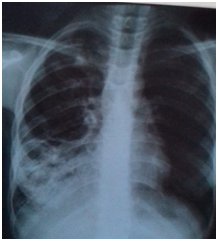

Female Patient (PT) 15 years old, referred to our hospital after more than 6 months of recurrent infections in right lower lobe (RLL) of the lung Figure A1 & A2. The PT had investigated, CXR was done Figure A3. The sputum was negative for TB many times. Bronchoscopy was done, no foreign body, no tumor, no anomalies, the washing was tested for TB and was negative. The decision for surgery was taken, the RLL was contracted, nodular and solid. RL Lobectomy was done. At second day post operation the PT had fever, sweat, no appetite and bad general condition. CXR revealed bilateral diffuse infiltrations. Figure B1. We decided to give her a trial TB treatment. After five days PT began to respond clinically. So TB treatment for minimum 6months is ordered.

A1 22-1-2019

A2 6-2-2019

A3 19-6-2019